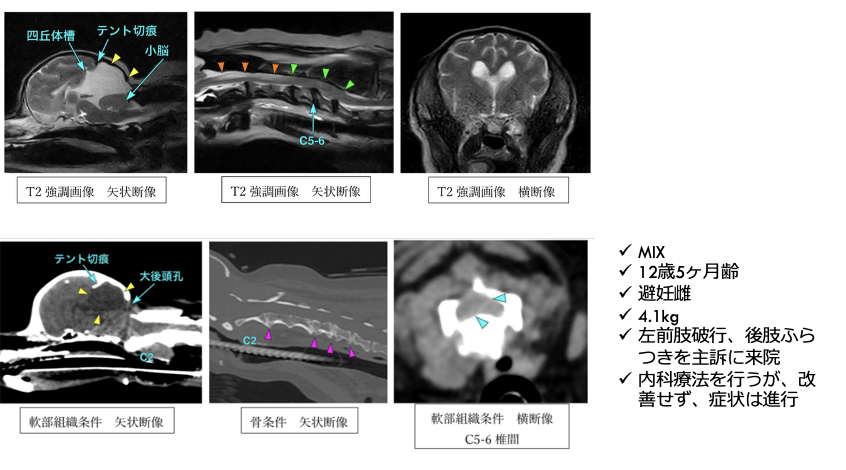

左前肢破行、後肢ふらつきを主訴に来院しました。CT・MRI撮影より、C5-6の椎間板ヘルニア、小脳背側のくも膜下嚢胞が認められました。症状が軽度から中等度、また小脳背側にくも膜下嚢胞が認められ麻酔のリスクなどを考慮し、まずは内科療法から行いました。2か月後症状の改善が認められず、症状も進行し、起立・歩行困難となりました。

左前肢破行、後肢ふらつきを主訴に来院しました。CT・MRI撮影より、C5-6の椎間板ヘルニア、小脳背側のくも膜下嚢胞が認められました。症状が軽度から中等度、また小脳背側にくも膜下嚢胞が認められ麻酔のリスクなどを考慮し、まずは内科療法から行いました。2か月後症状の改善が認められず、症状も進行し、起立・歩行困難となりました。

C5-6椎間板ヘルニア、小脳背側くも膜下嚢胞

C5-6椎間板ヘルニア、くも膜下嚢胞と診断した